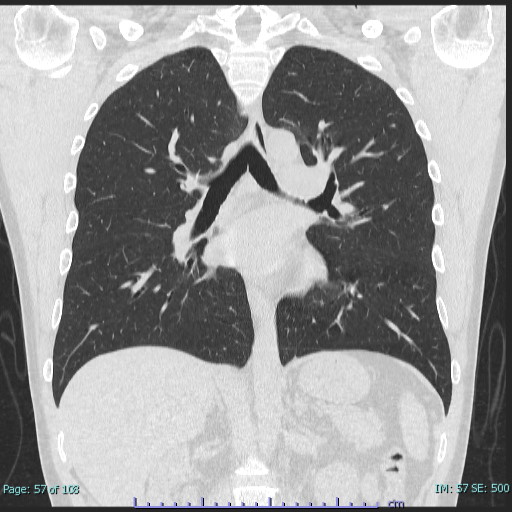

肺

胸部CT 冠状断像

CTの方が圧倒的に優れています。(MRIで空気は描出できません)

肺がんや肺野病変の存在、鑑別診断はMRIよりCTが優れています。

MRIの欠点は、肺野(空気)の信号強度が低く結節性、炎症性病変の検出能に限界があること、心拍によるアーチファクト(ノイズ)が大きいこと、石灰化の存在診断が困難なこと、空間分解能がCTに劣ることがあげられます。

また、肺がんは胸部X線検査を行っているから大丈夫と思っている方は注意が必要です。

胸部X線検査は、肋骨や横隔膜に重なっている部分や非常に小さな肺がんは見つからず、肺の60~70%しか見えていないとされています。

CT検査の場合は身体を輪切りにした状態で撮影をしますので、肺が心臓や胸椎、横隔膜によって見えづらくなってしまうといったことがなく、小さな病変も描出できますので、より精密な検査を行うことができます。

健診や人間ドックの胸部CTの目的は、主に肺がんや肺野病変の有無を検査することが重要となりますので、CT検査をおすすめします。